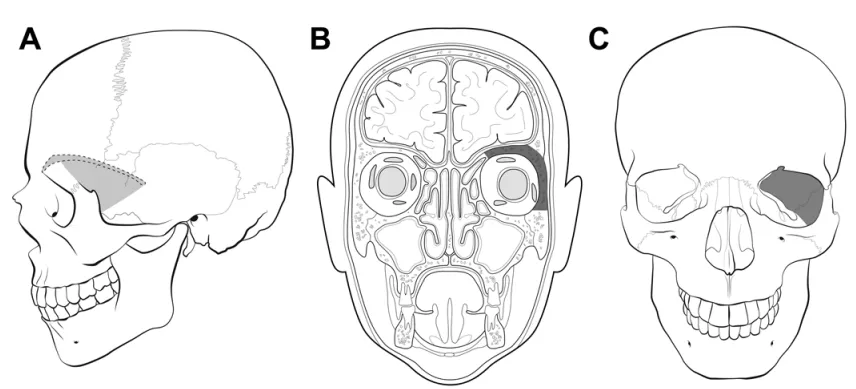

阴影区域标示了从外侧观(a)、冠状位内侧观(b)和冠状位外侧观(c)所见需切除的骨质范围。阴影部分包括眶外侧壁、眶上壁、视神经管及前床突。保留了眶缘。